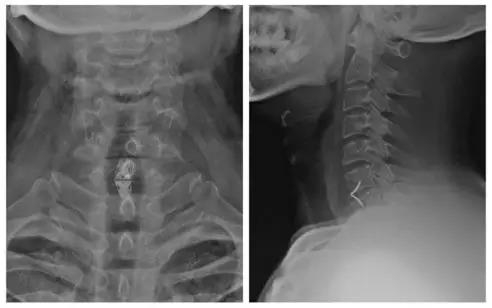

术前X线正侧位片

术前过屈过拉伸

术后X线正侧位

患者:李某,女,52岁

主诉:右手中指、环指麻木20余天,并双下肢踩棉感20余天

诊断:

1.颈椎病(混合型);

2.后纵韧带骨化症(C2-4)。